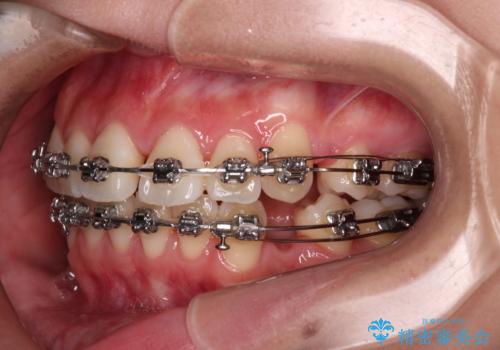

- 矯正装置

- メタルブラケット

- 1年10ヶ月

- 10-30回

- 前歯がくちばしのように飛び出していることを気にして来院された患者様です。

唇が前方に突出している横顔が気になっているため、上下左右の第一小臼歯4本を抜歯し、ワイヤー装置にて矯正治療を行うこととしました。